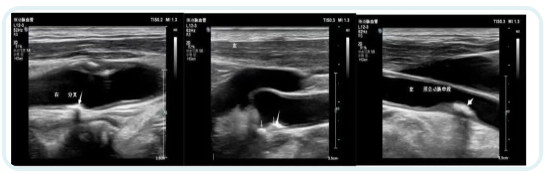

在颈动脉超声检查中,不少人发现自己的检查报告中有“强回声斑块”“低回声斑块”“混合回声斑块”,颈动脉斑块形成,让人很容易焦虑,会想到是否和脑梗有关?需不需要吃药或者手术治疗?究竟哪些斑块是有风险的?

颈动脉使用彩色超声检查,报告单上的各种“回声”代表着斑块的内容物与质地。硬斑块——等回声与强回声代表超声波遇到了较硬的物质,所以反射回声较多。表示斑块内可能含有较多纤维组织,或有钙化,为稳定斑块,也称为“硬斑块”。软斑块——无回声与低回声、混合回声代表超声波被吸收,所以反射较少,表示斑块内可能有出血、炎症或是有较大的脂质内核,为不稳定斑块,也称为“软斑块”。如果出现“混合回声”则代表回声区域情况复杂,可能是坏死细胞形成的钙化、出血、炎症渗出、较大脂质核心等混杂在一起,为不稳定斑块,是危险性较大的软斑块。